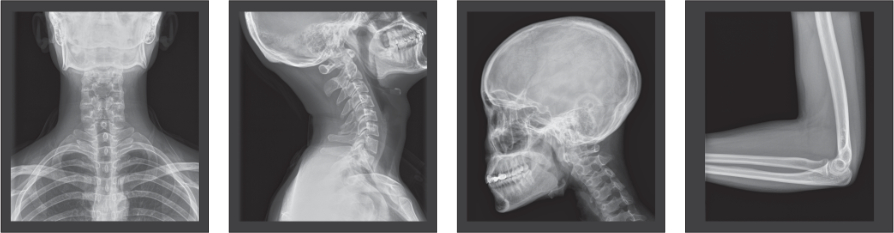

Tecnologías avanzadas que proporcionan una excelente calidad de imagen:

La calidad de los rayos X se ve garantizada gracias a un tubo duradero y a un generador de mayor frecuencia. La mayor eficiencia cuántica del panel detector plano permite obtener una mejor calidad de la imagen, al mismo tiempo que se reduce la dosis de rayos X necesaria para el diagnóstico clínico.